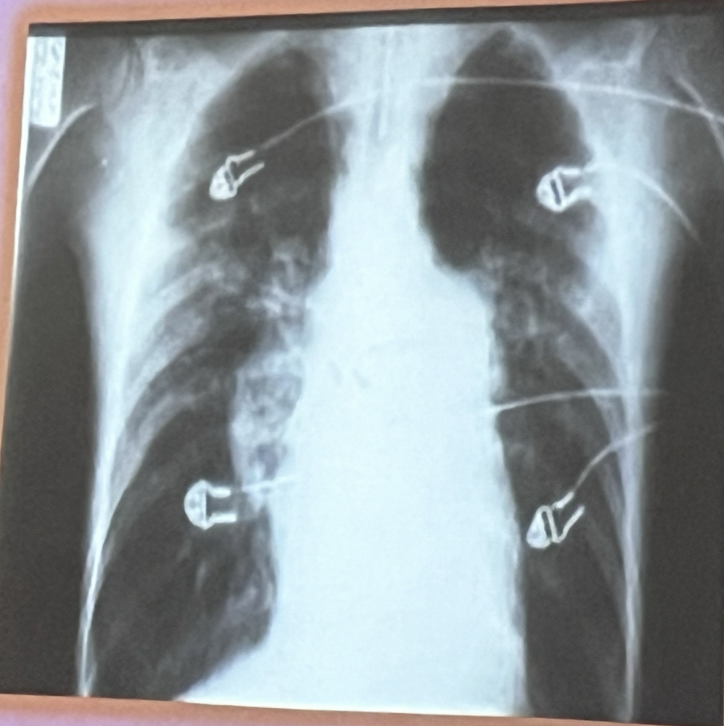

Rx: Patrón bronquial

A

• Aumento de la trama vascular

• Patrón de riel

• Hiperinsuflación